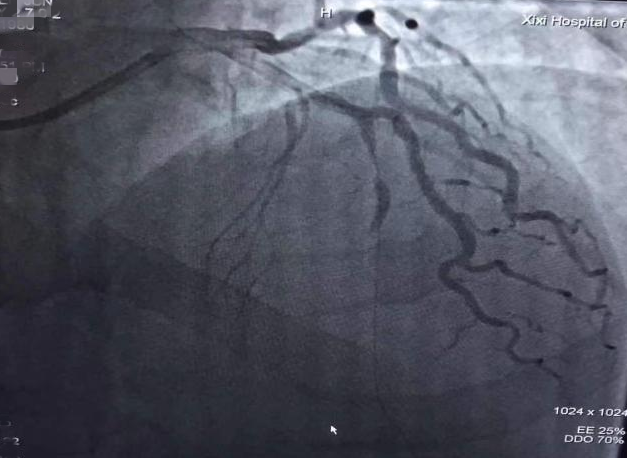

突发胸痛,紧急抢救保命

术后,负责完成此次抢救工作的心血管内科方天富主任表示,张先生这次真是万幸。时间就是“心肌”,如果出现胸闷、胸痛无法缓解的情况,应在陪护下尽快就医,千万不要自行开车或打车前往医院,最好及时拨打120,避免来院途中发生意外。